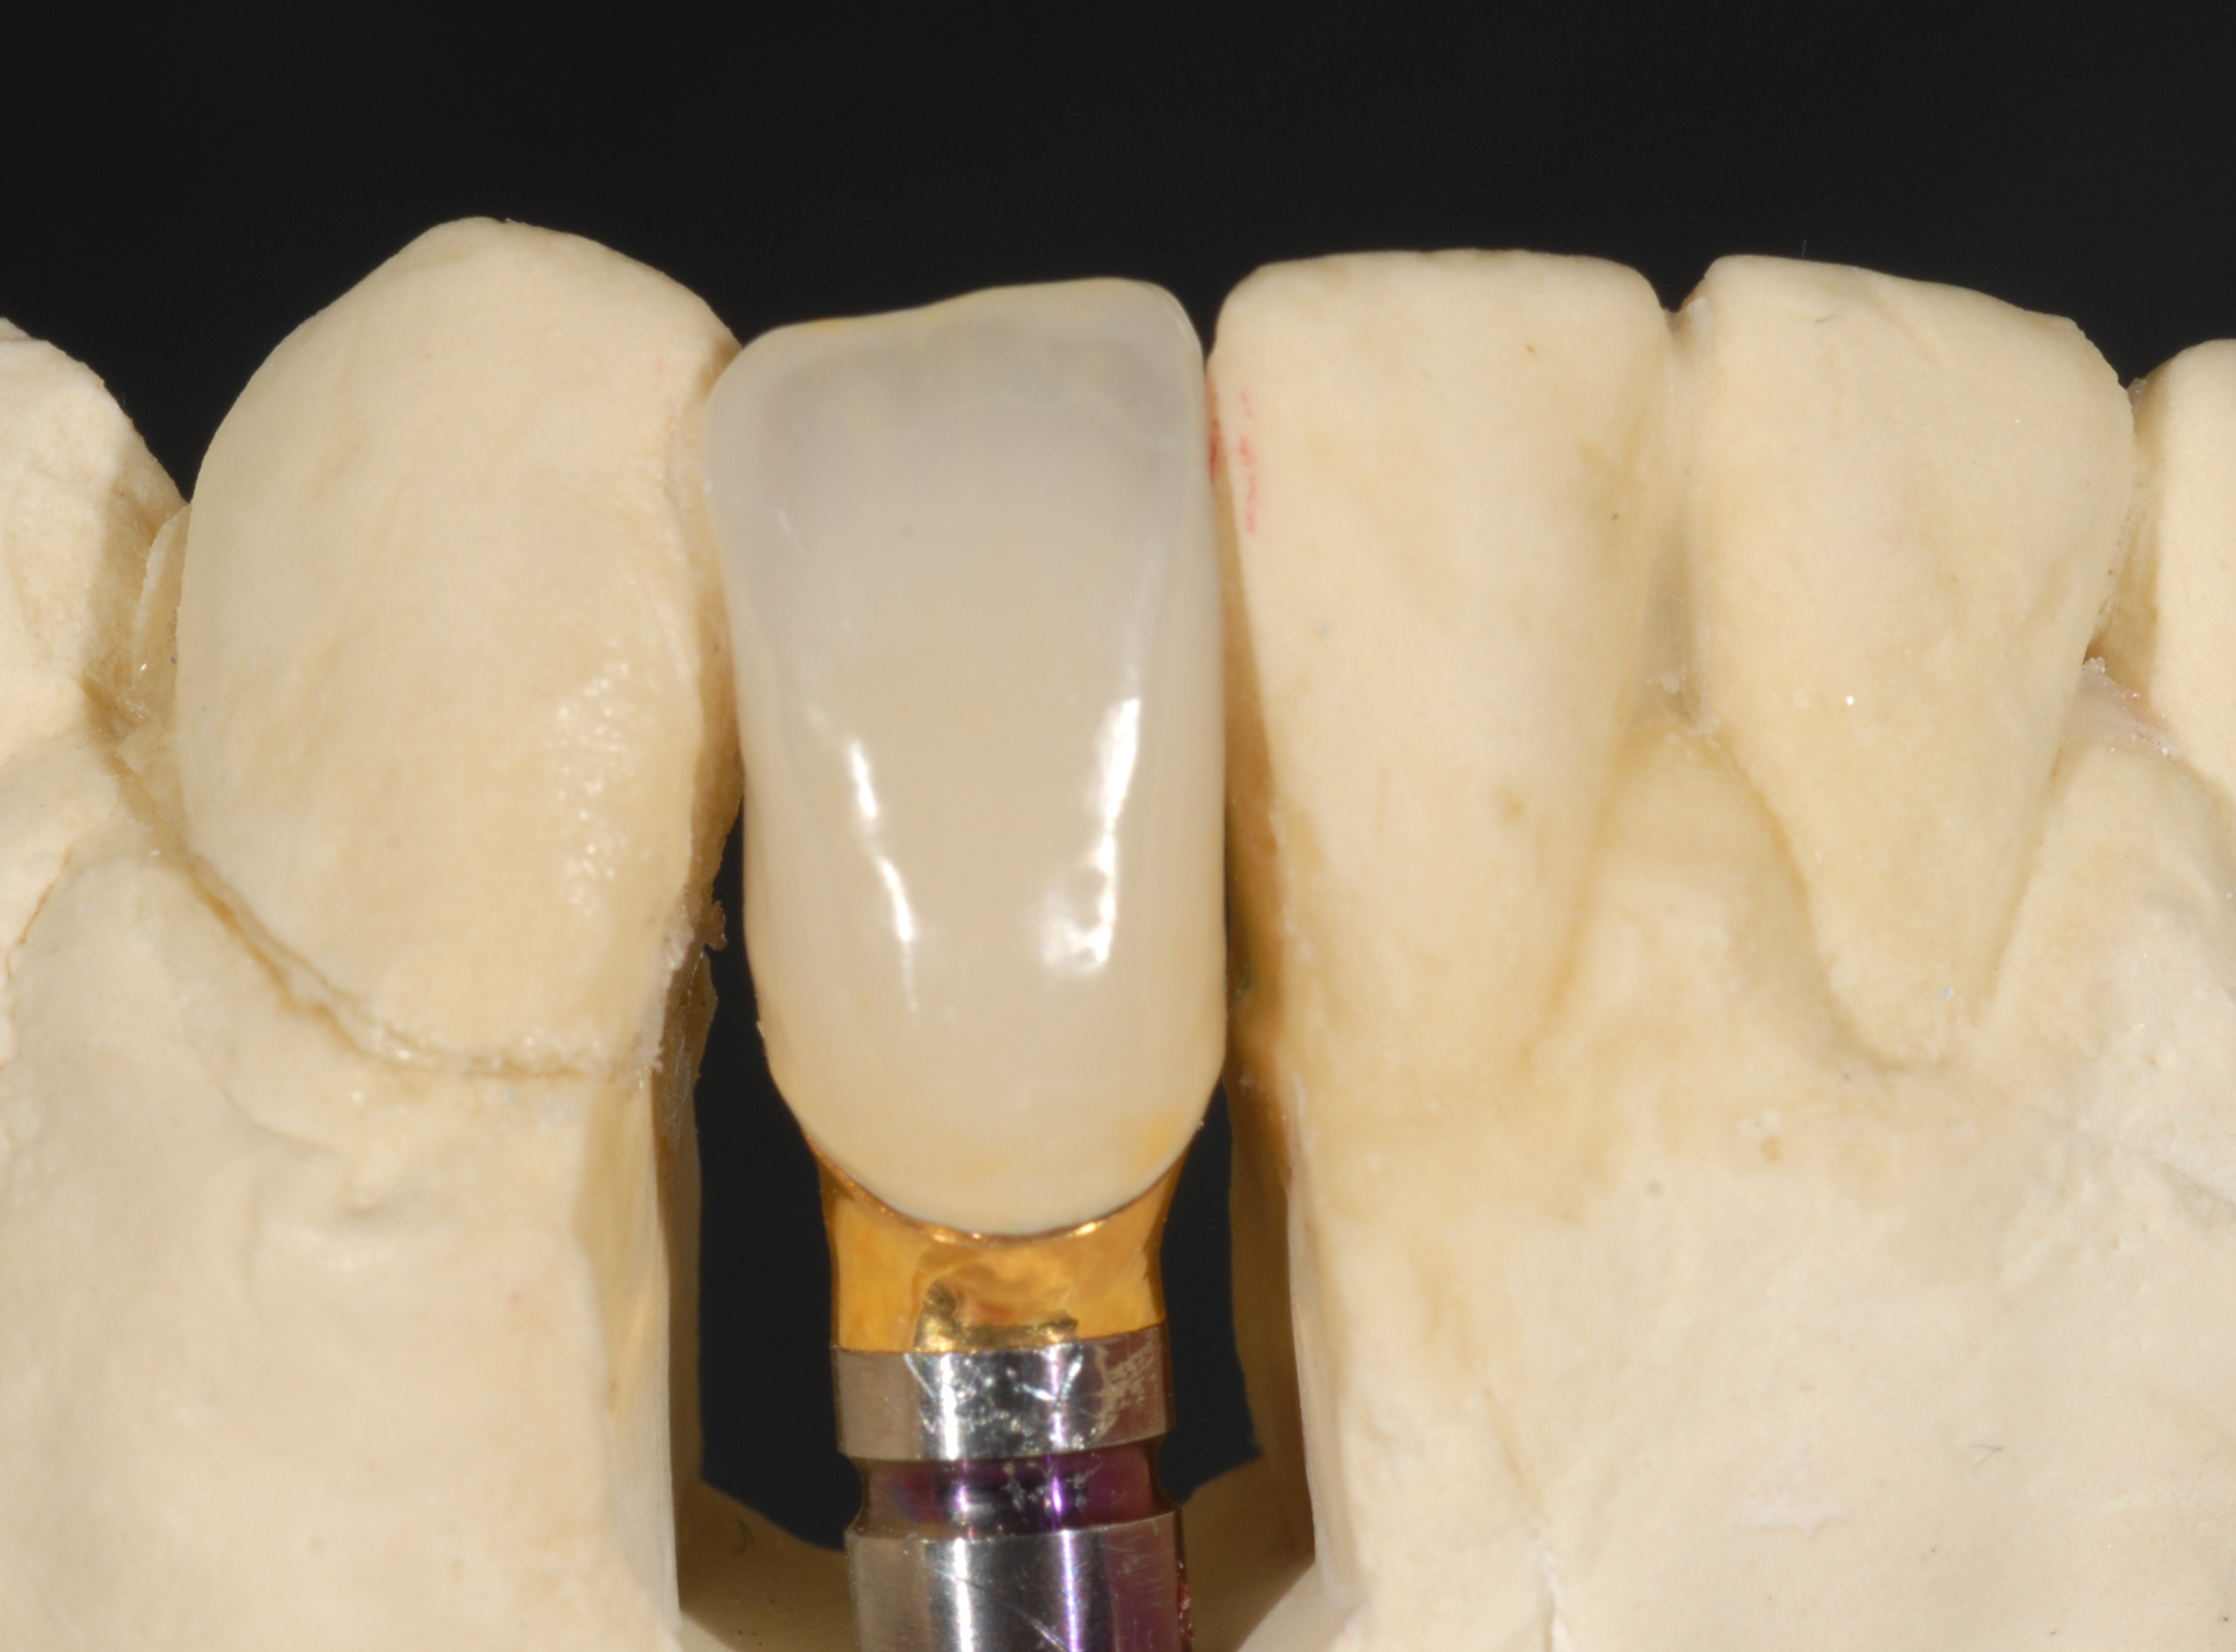

Fig 11. A custom alloy-based (semi-noble metal) abutment was fabricated. Metallic alloy was selected due to the compromise in abutment diameter as well as the severe angulation of the implant (left), lending to a thin facial abutment thickness of material for strength (right).

Figure 11

Fig 12. A cement-retained metal-ceramic crown was fabricated as the definitive restoration and luted with a provisional cement to allow the crown to be retrieved in the future.

Figure 12

Fig 44. A new metal-alloy abutment was fabricated for the narrow-diameter implant with a cement-retained metal-ceramic crown.

Figure 44